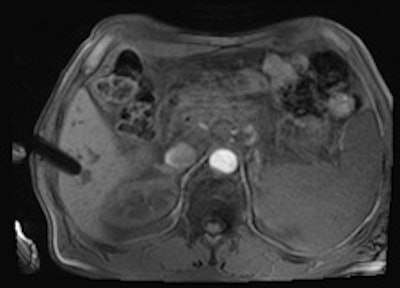

A 50-year-old man with history of pancreatic carcinoma underwent a CT-guided biopsy (above), which was nonconclusive (pathology result: normal liver tissue). Three weeks later, an MR-guided biopsy (below) was performed, and the biopsy revealed a cavernous hemangioma. Images courtesy of Dr. Rüdiger Hoffmann.